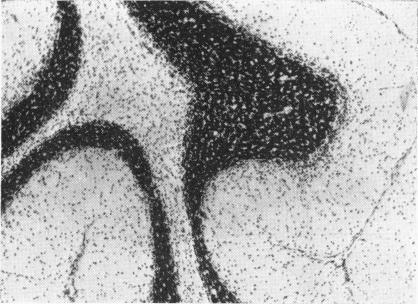

CROME L

Arch Dis Child. 1962 Aug;37(194):415-21. doi: 10.1136/adc.37.194.415.